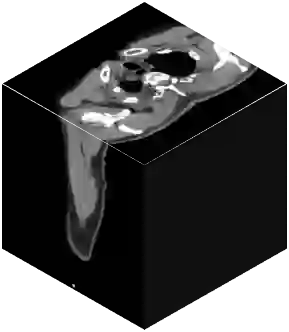

Vision transformers, with their ability to more efficiently model long-range context, have demonstrated impressive accuracy gains in several computer vision and medical image analysis tasks including segmentation. However, such methods need large labeled datasets for training, which is hard to obtain for medical image analysis. Self-supervised learning (SSL) has demonstrated success in medical image segmentation using convolutional networks. In this work, we developed a \underline{s}elf-distillation learning with \underline{m}asked \underline{i}mage modeling method to perform SSL for vision \underline{t}ransformers (SMIT) applied to 3D multi-organ segmentation from CT and MRI. Our contribution is a dense pixel-wise regression within masked patches called masked image prediction, which we combined with masked patch token distillation as pretext task to pre-train vision transformers. We show our approach is more accurate and requires fewer fine tuning datasets than other pretext tasks. Unlike prior medical image methods, which typically used image sets arising from disease sites and imaging modalities corresponding to the target tasks, we used 3,643 CT scans (602,708 images) arising from head and neck, lung, and kidney cancers as well as COVID-19 for pre-training and applied it to abdominal organs segmentation from MRI pancreatic cancer patients as well as publicly available 13 different abdominal organs segmentation from CT. Our method showed clear accuracy improvement (average DSC of 0.875 from MRI and 0.878 from CT) with reduced requirement for fine-tuning datasets over commonly used pretext tasks. Extensive comparisons against multiple current SSL methods were done. Code will be made available upon acceptance for publication.